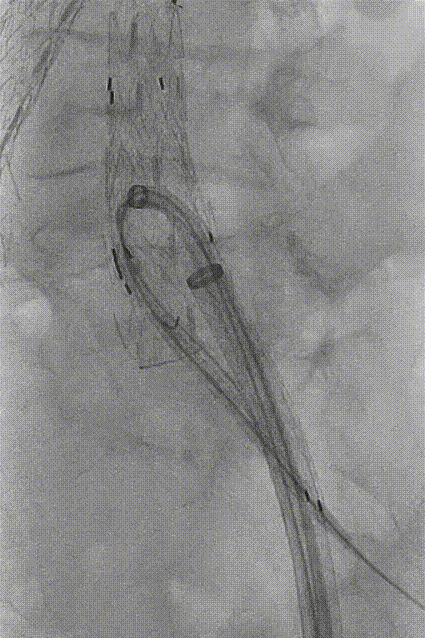

将20Fr鞘沿泥鳅导丝硬头端送至IBE主体支架分叉处,再导入GORE DSF1245鞘经20Fr鞘沿泥鳅导丝翻山至短腿开口。

gore医疗怎么样「漫腹精论」独具匠心 推陈出新——同侧IBE支架内翻山重建髂内动脉治疗EVAR术后内漏病例报道_https://www.jmylbn.com_新闻资讯_第16张

翻山至IBE短腿开口

导丝配合导管沿DSF1245鞘选至髂内远端,交换Amplatz导丝,植入GORE髂内分支支架HGB161207(16mm-12mm-70mm),退鞘,手推造影确认位置后释放。髂外动脉起始段及髂内动脉中段见受压。导入球囊(8mm*40mm)扩张髂内动脉狭窄处,并予以CODA球囊扩张髂外动脉起始段狭窄处。

gore医疗怎么样「漫腹精论」独具匠心 推陈出新——同侧IBE支架内翻山重建髂内动脉治疗EVAR术后内漏病例报道_https://www.jmylbn.com_新闻资讯_第18张

植入髂内分支

gore医疗怎么样「漫腹精论」独具匠心 推陈出新——同侧IBE支架内翻山重建髂内动脉治疗EVAR术后内漏病例报道_https://www.jmylbn.com_新闻资讯_第19张

释放髂内分支